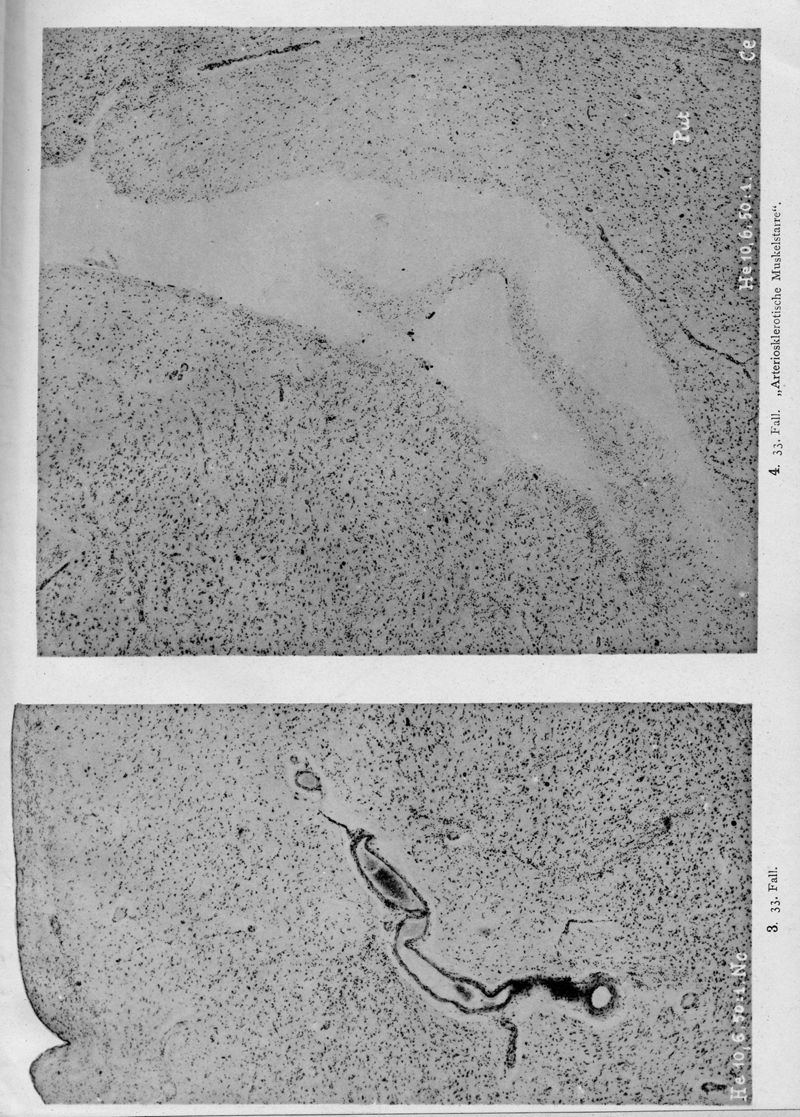

VOGT, Cécile / VOGT, O.

In : Journal für Psychologie und Neurologie,

1920, Vol. 25, pp. 627-846